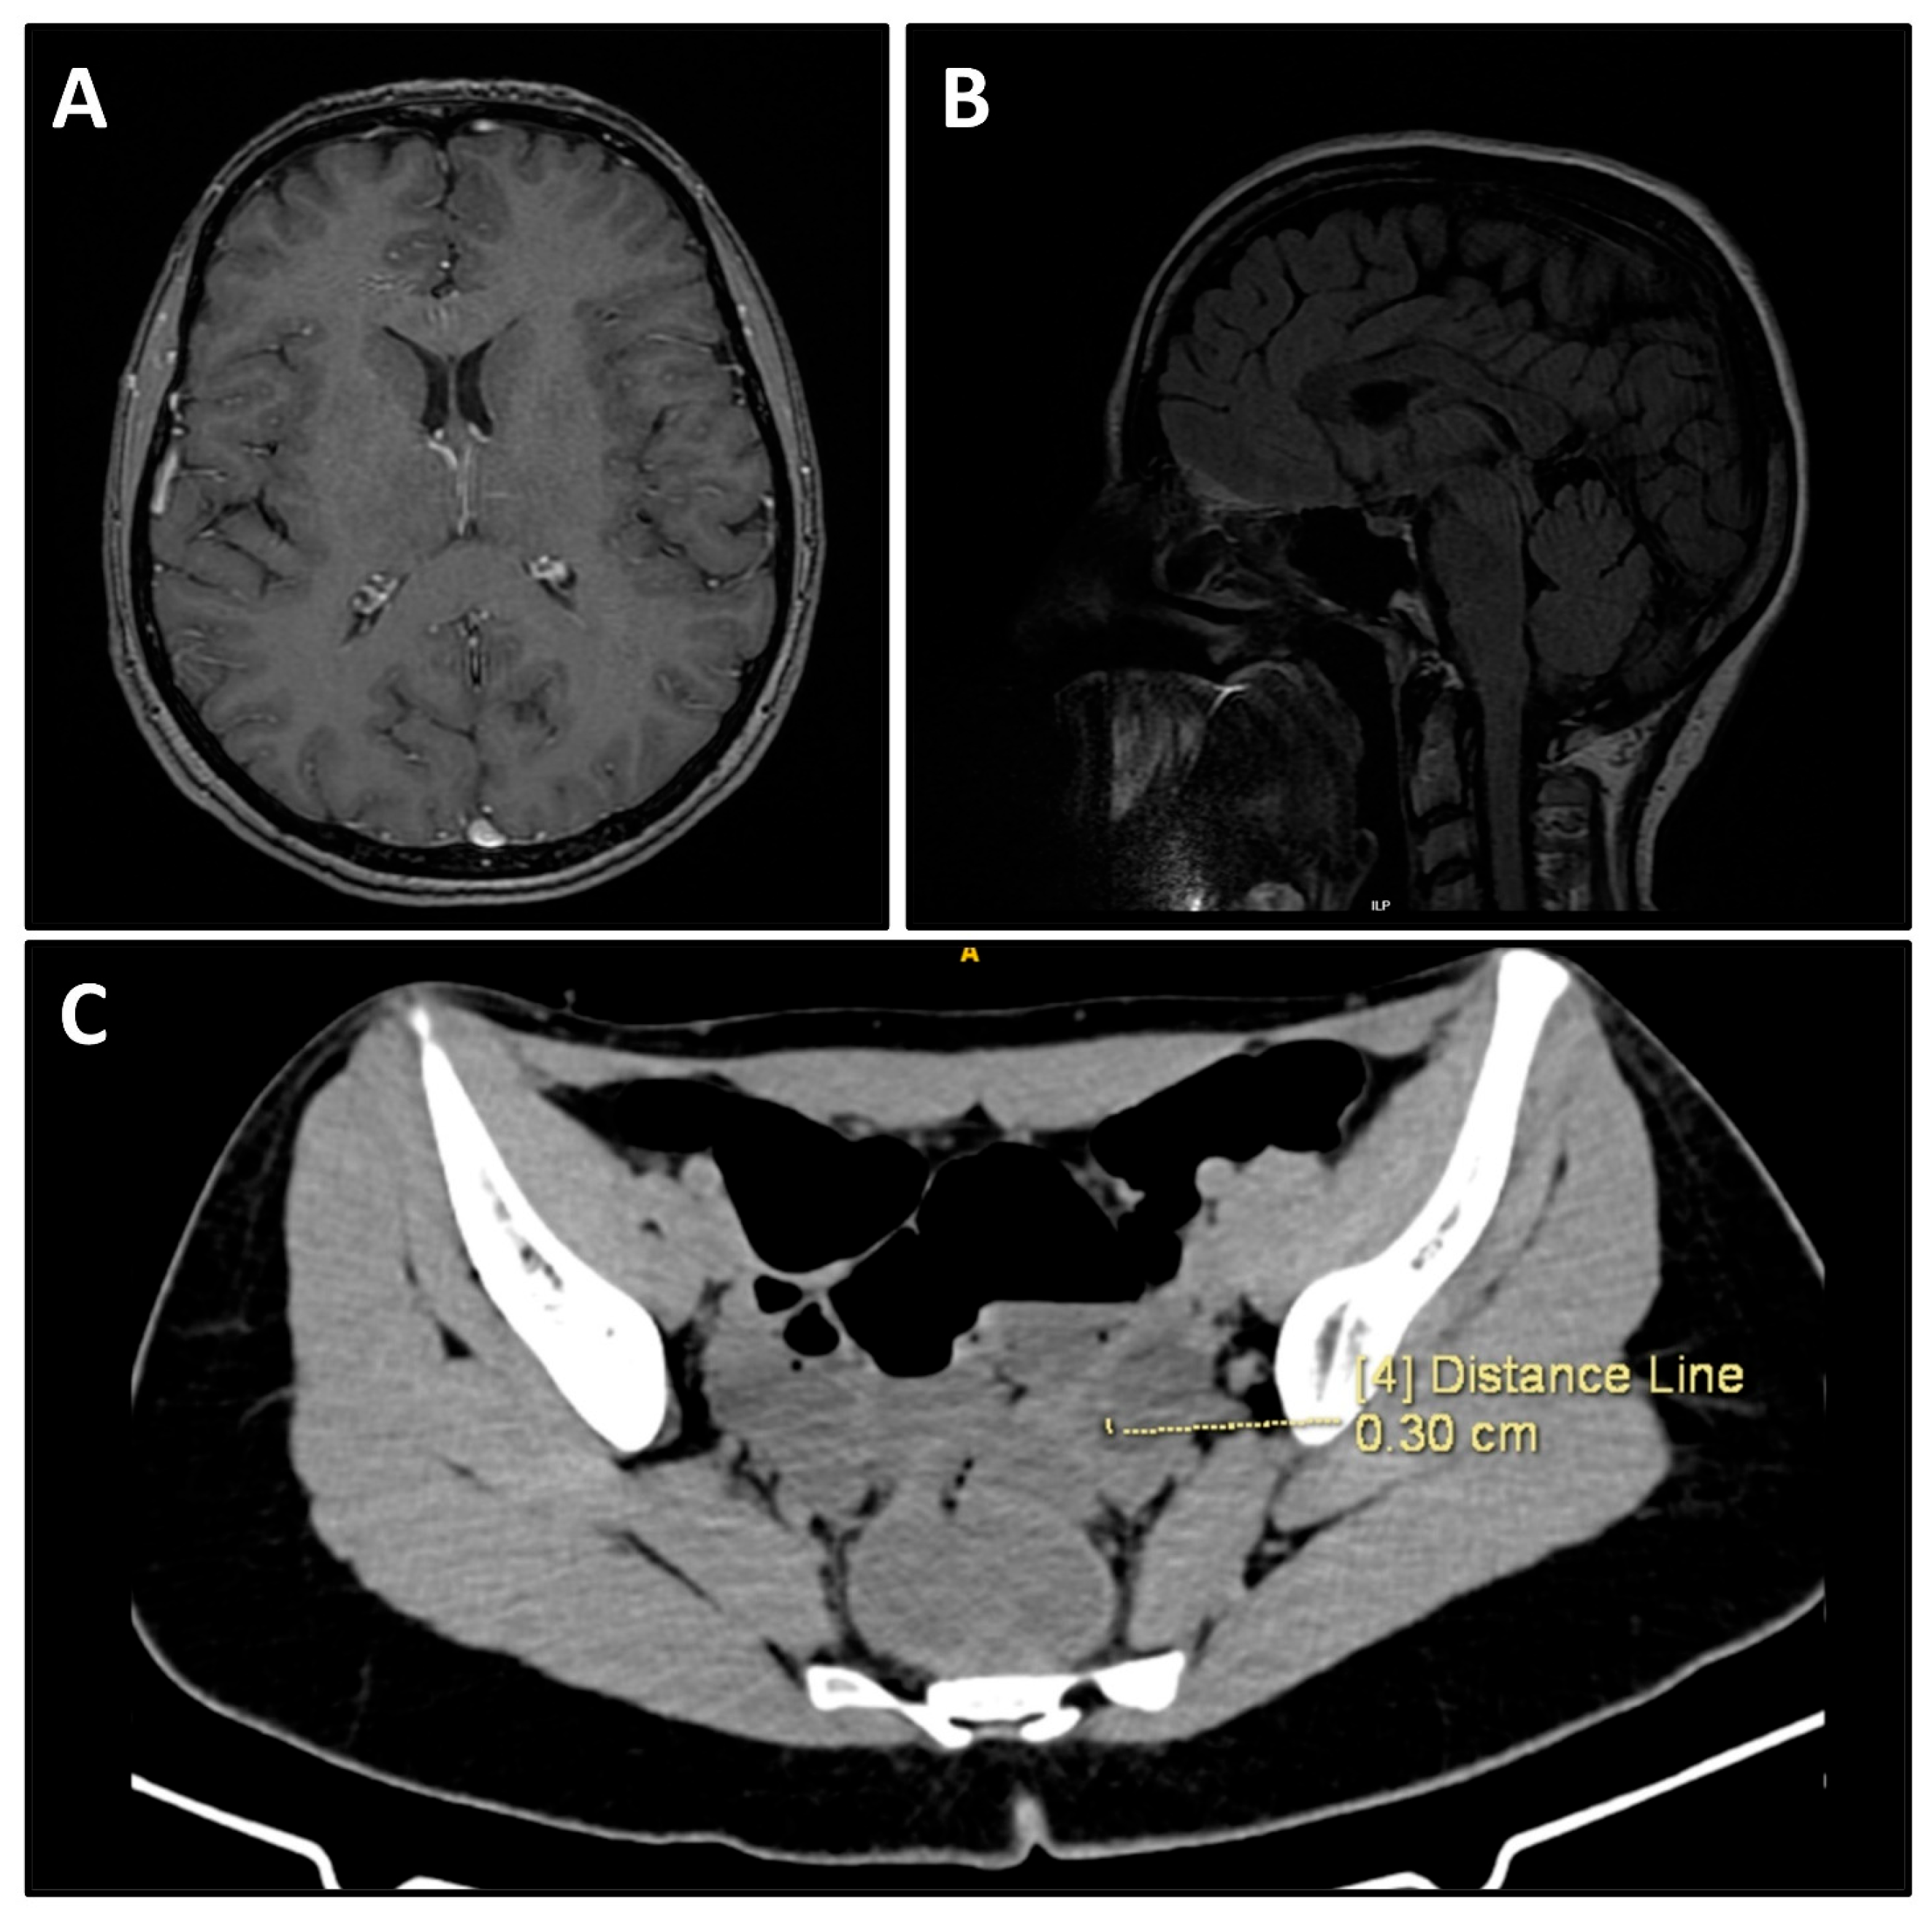

Additional immunofluorescence analysis on 3 June 2025 demonstrated findings consistent with inflammatory meningeal changes. Brain MRI showed no structural abnormalities (Figure 2A,B). Neurology consultation recommended high-dose intravenous methylprednisolone (1000 mg/day for 3 days followed by 500 mg/day). Due to clinical severity, she was transferred on 5 June 2025 to the intensive care unit of Alexandrovska University Hospital for continued management. Contrast-enhanced CT of the abdomen and pelvis performed on 5 June 2025 revealed a 27 × 19 mm cystic lesion in the left ovary containing fat and calcifications, most consistent with a mature cystic teratoma (Figure 2C).

Figure 2. Imaging diagnostics. (A) Normal axial MRI of the brain in T1. (B) Normal sagittal MRI of the brain in T2 FLAIR. (C) CT scan of the lesser pelvis demonstrating a 27 × 19 mm cystic lesion in the left ovary.